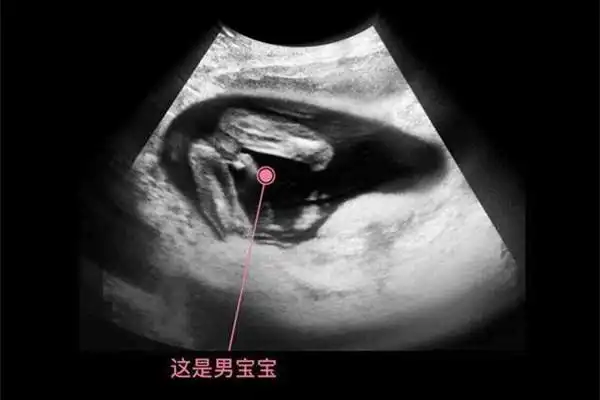

12周nt明显三条线生男孩这都是宝妈的真实经历

孕12周nt检查显示有三个亮点是男孩还是女孩

[试管婴儿]b 超图 大神帮看看是传说中的三条线么?

2,四维3个亮点是男孩:怎样可以看出四维彩超上是男孩还是女孩